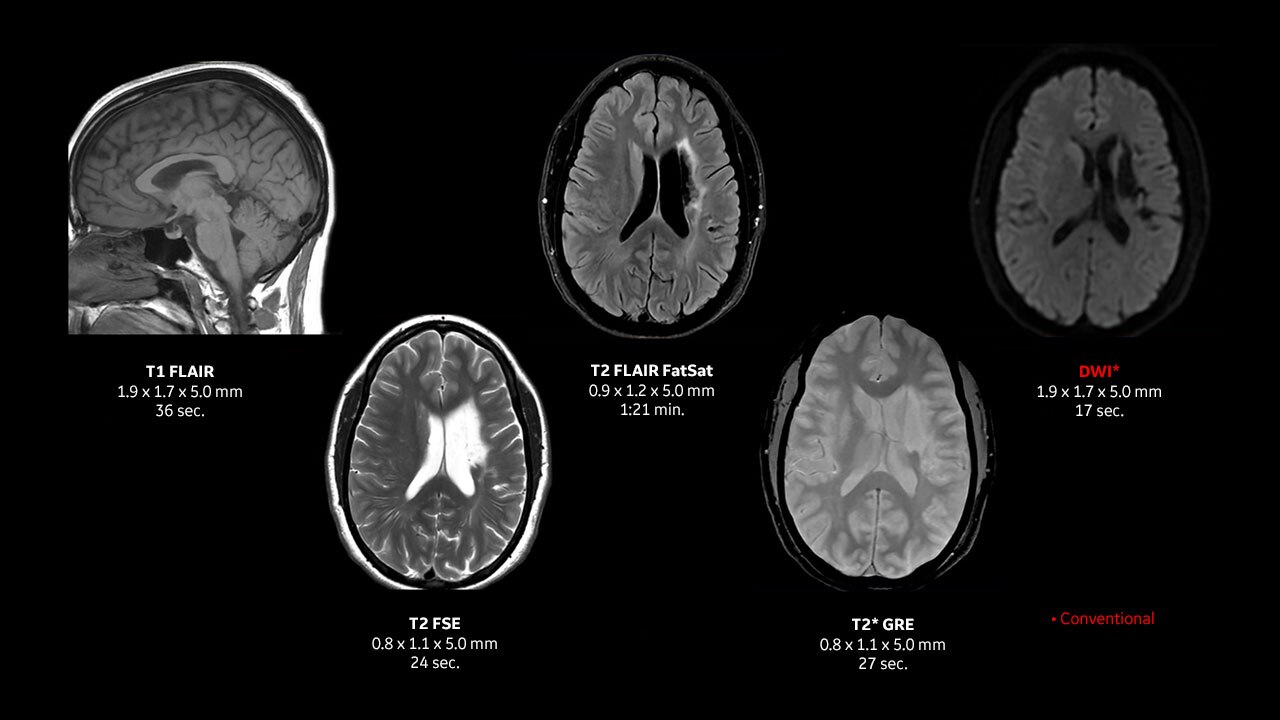

With the Voluson Expert 18, increase your capability and confidence with superior imaging, powered by our most advanced architecture yet. Experience more detailed 2D/3D/4D and color Doppler images to enhance visualization in your obstetric and gynecological cases.

Unlocks new imaging and processing power to achieve high resolution, detailed images